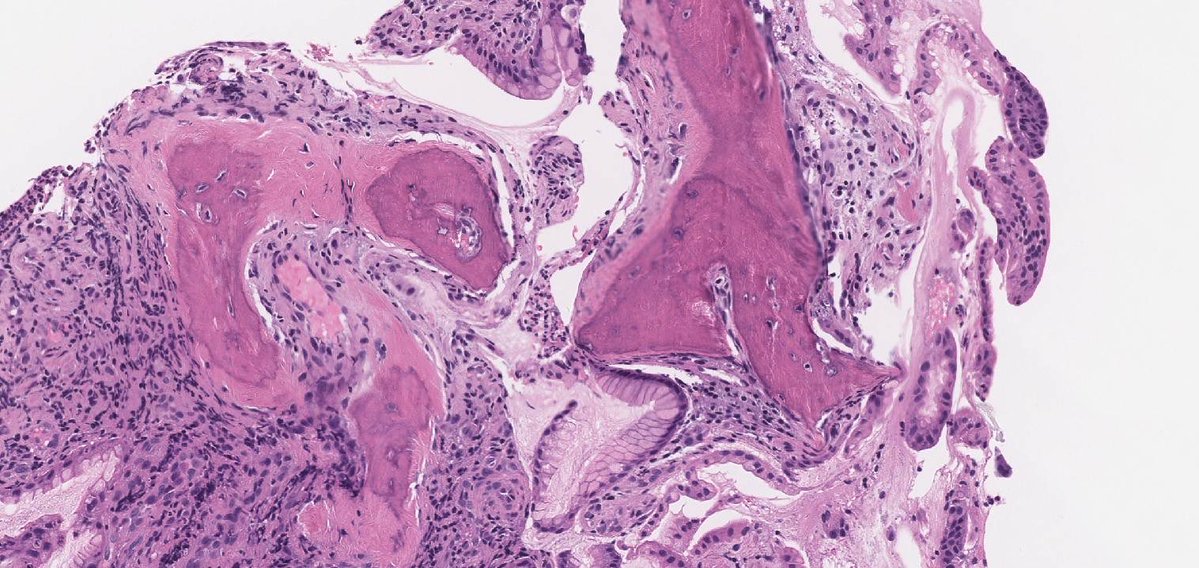

#GUpath #beautyinb9 mimic of prostate cancer on bx: 🔬basal cell hyperplasia